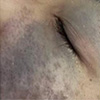

从现有观察来看,太田痣更偏爱这类人群!快看看你是不是高危对象,并非毫无规律可循。亚洲人群中的发生比例相对更高,尤其是肤色偏黄、面部轮廓柔和的人群中更为常见。此外,女性出现的概率也略高于男性,这或许与激素水平变化存在一定关联。值得注意的是,这种表现通常单侧分布,集中在眼周、颧骨、前额等区域,呈青灰、蓝黑或褐色,边界模糊但整体稳定,很少自行消退。